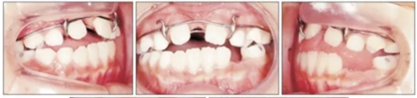

第二階段(圖5,6;表2)

面弓矯治包括在混合牙列及早期恒牙列的傳統(tǒng)牙支抗面弓及恒牙列的骨支抗面弓。由于患者曾行腭成形術(shù),為了將矯治力傳遞到上頜骨,使用唇舌弓而不是快擴(kuò)。8歲5月時(shí)開始用面弓聯(lián)合唇舌弓矯治(500g/邊,與合平面呈30°向下),持續(xù)3年6月?;颊吲宕鲿r(shí)間為12-14時(shí)/天。

上頜前磨牙萌出后取出唇舌弓,上固定矯治器以排齊上頜牙列,該階段面弓暫時(shí)停止使用。